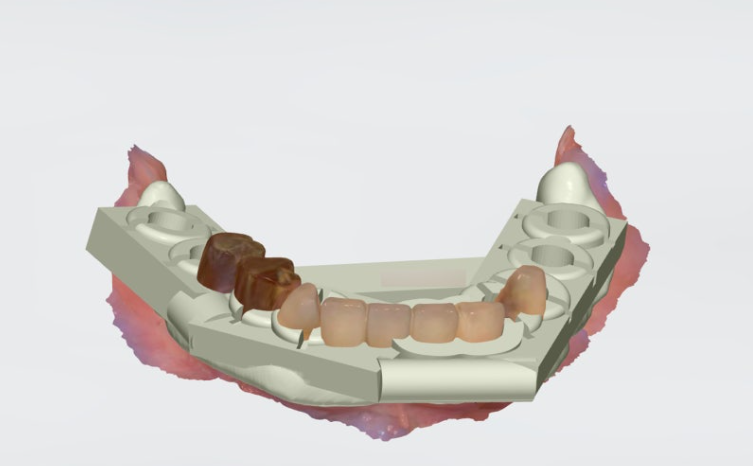

전악 임플란트는 식립 위치에 따라 결과가 크게 달라질 수 있기 때문에 구강스캐너와 3D CT를 활용한 모의 수술, 그리고 디지털 가이드를 통한 수술 계획이 매우 중요합니다. 이 장치는 환자의 구강 구조를 정확히 반영하여 잇몸을 필요한 만큼 절재하고, 정밀한 각도로 인공치근을 심을 수 있도록 도와줍니다. 그 결과 출혈과 붓기, 통증을 줄일 수 있으며 회복 속도도 빨라집니다.

보철 식립 전 힐링 어버트먼트 장착

임플란트 식립 후에는 힐링 어버트먼트를 장착하여 잇몸을 안정적으로 유도합니다. 이 장치는 보철물이 올라가기 전까지, 잇몸 조직을 보호하고 세균 유입을 차단하는 역할을 합니다. 이후 지대주를 결합하고, 환자 맞춤형 보철물을 제작해 최종적으로 심미성과 기능까지 회복하게 됩니다.